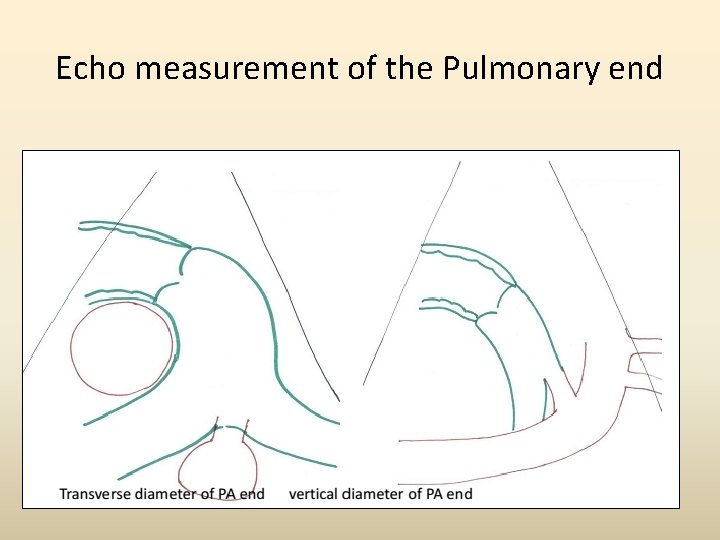

Echo measurement of the Pulmonary end